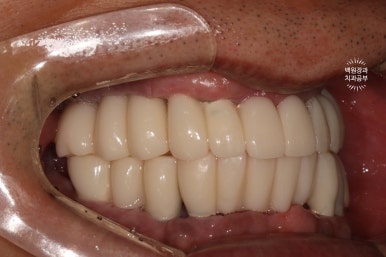

이렇게 보면 측면 모습도 상당히 괜찮고....

잘 보시면 치아와 치아 사이에 틈이 있는 것을 보실 수 있으실텐데요, 이 경계는 앞니 보철물/어금니 보철물의 경계로 추후에 보철물의 수리가 용이하기 하기 위함입니다. 더불어 치실을 쓸 수 있게 하는 공간으로 반드시 필요한 포인트!

이젠 치아가 생겨서, 식사를 하실 수 있게 되었습니다.

잘 제작된 보철물은 앞니로 면도 끊어먹을 수 있어서 환자분들께 크나큰 만족감을 줍니다.